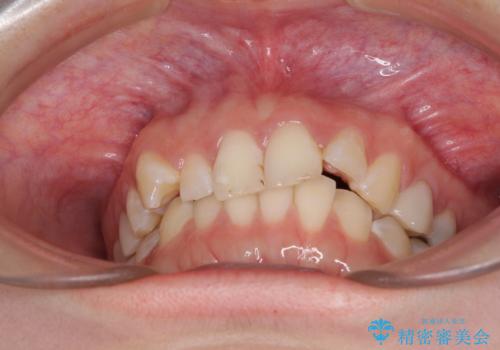

- 前歯の歯列不正を気にして来院された患者様です。

インビザラインでの矯正治療を希望されていましたが、奥歯の咬み合わせがインビザライン単独では改善困難と判断されたので、補助装置を併用することとしました。

まずは裏側の装置やワイヤー矯正を用いて歯列幅の狭い上顎を側方に拡大しつつ全体を後方に移動させ、その後インビザラインにて歯列を整えることとしました。